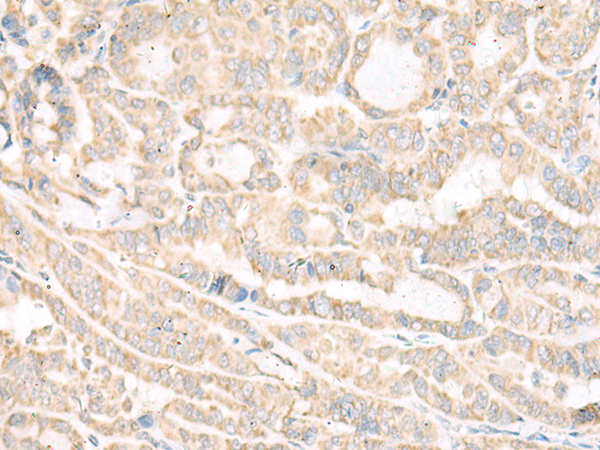

ELISA, IHC |

IHC positive control: |

Human thyroid cancer and Human cervical cancer |